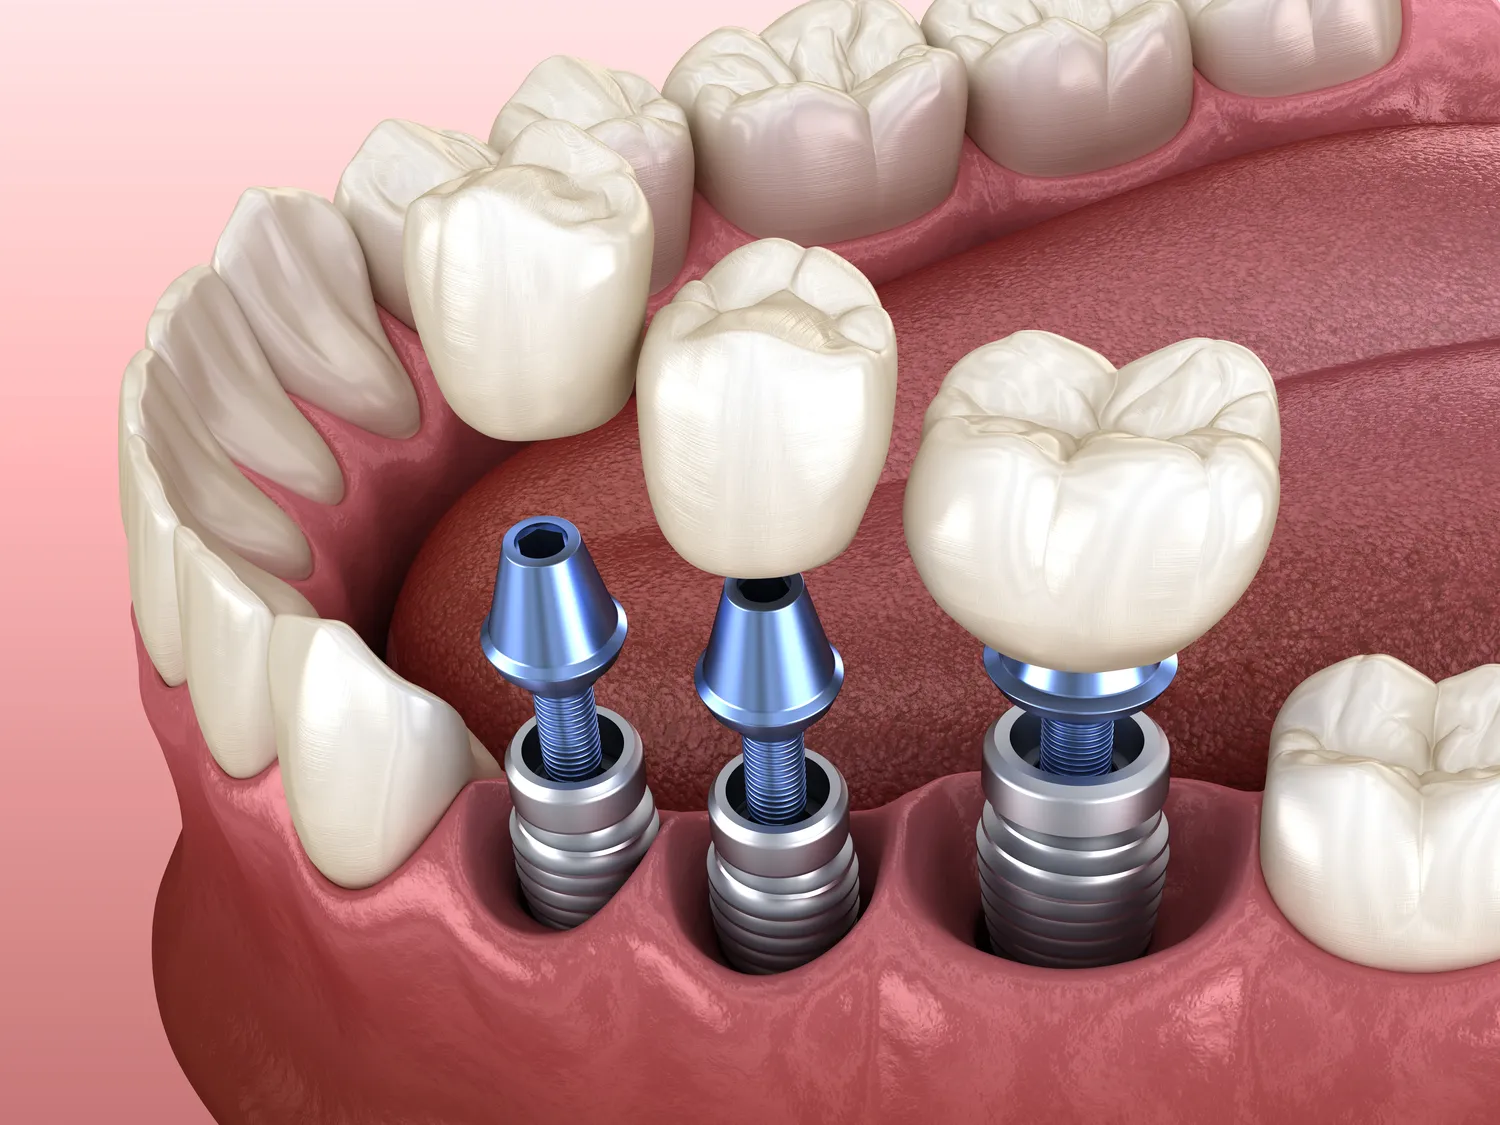

Średnie zarobki stomatologów różnią się znacznie w zależności od specjalizacji, co warto uwzględnić przy analizie tego zawodu. Stomatolodzy ogólni zazwyczaj zarabiają mniej niż specjaliści, którzy posiadają dodatkowe kwalifikacje. Na przykład ortodonci mogą liczyć na wynagrodzenia rzędu 15-20 tysięcy złotych miesięcznie, szczególnie jeśli pracują w dużych miastach i mają ustaloną bazę pacjentów. Chirurdzy stomatologiczni również osiągają wysokie dochody dzięki skomplikowanym zabiegom oraz rosnącemu zapotrzebowaniu na implanty zębowe i inne procedury chirurgiczne. Specjaliści zajmujący się estetyką uśmiechu również cieszą się dużym zainteresowaniem i mogą liczyć na wysokie wynagrodzenia za swoje usługi. Warto jednak pamiętać, że wynagrodzenia te mogą się różnić w zależności od regionu kraju oraz renomy gabinetu.

Różnice w zarobkach stomatologów pracujących w gabinetach prywatnych i publicznych są znaczące i warto je dokładnie przeanalizować. Stomatolodzy zatrudnieni w publicznych placówkach, takich jak przychodnie czy szpitale, często mają ustalone wynagrodzenie, które jest regulowane przez przepisy prawa oraz kontrakty z NFZ. W takim przypadku ich pensje mogą być znacznie niższe niż te oferowane w sektorze prywatnym. Średnie wynagrodzenie stomatologa w publicznej służbie zdrowia oscyluje wokół 5-8 tysięcy złotych miesięcznie, co jest kwotą znacznie niższą od zarobków stomatologów pracujących na własny rachunek. W gabinetach prywatnych wynagrodzenia mogą sięgać nawet 20 tysięcy złotych miesięcznie, zwłaszcza jeśli stomatolog specjalizuje się w bardziej skomplikowanych zabiegach. Dodatkowo stomatolodzy pracujący w sektorze prywatnym mają większą swobodę w ustalaniu cen za swoje usługi oraz elastyczność w organizacji pracy, co może przyciągać wielu specjalistów do tego sektora.